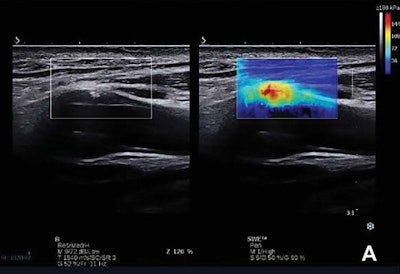

(A, above) Carotid plaque classified as Gray-Weale Type II shown with a B-mode and shear-wave elastography image. (B, below) The Young's modulus value of the plaque located in the anterior of the internal carotid artery was obtained using the Q-Box-Trace software tool. All images courtesy of the Journal of Ultrasound in Medicine.What's more, logistic regression and receiver operating characteristic (ROC) analysis suggested that the combination of the mean Young's modulus with stenosis rate could yield increased sensitivity and specificity for identifying symptomatic carotid plaques, according to the researchers.